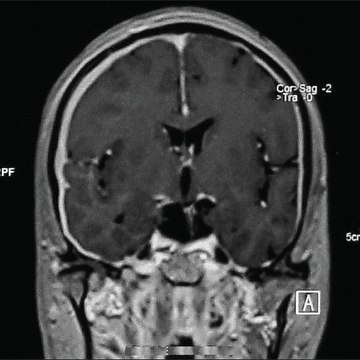

Wegeners granulomatosis (WG) is a rare disease of uncertain cause. It is characterized by inflammation in a variety of tissues, including blood vessels .\r<br>\r<br>Wegeners granulomatosis (also known as granulomatosis with polyangiitis) is a type of vasculitis that affects small and medium blood vessels. Symptoms can .\r<br>\r<br>AKA hepatolenticular degeneration is an inherited disorder that causes too much copper to accumulate in your liver, brain and other vital organs.\r<br>\r<br>Churg-Strauss syndrome (also known as eosinophilic granulomatosis with polyangiitis) is a type of vasculitis that affects small and medium blood vessels.